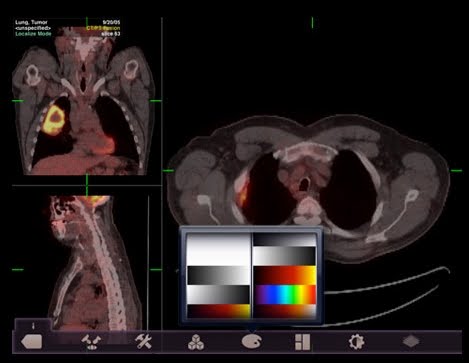

ResolutionMD Mobile (imagem abaixo) roda em um servidor OEM e é acessado por rede Wireless, permite pesquisar em qualquer PACS conectado e exibe qualquer imagem DICOM. Mas o que você vê não é armazenada no IPAD, portanto os problemas com privacidade dos dados dos pacientes são minimizados.

![]() |

| ResolutionMD Mobile |